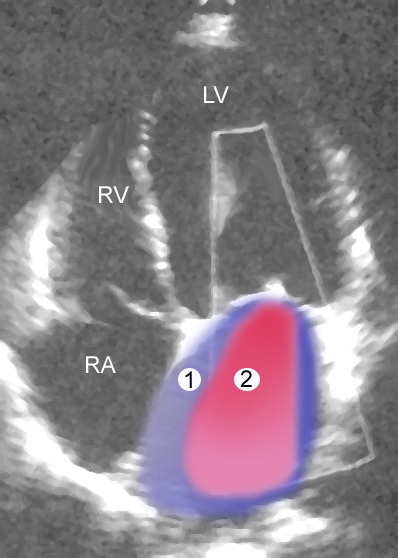

Mitral regurgitation occurs when blood flows from the left ventricle into the left atrium during systole and is mainly caused by mitral valve prolapse.

Causes of mitral regurgitation include:

- Acute rheumatic heart disease

- Papillary muscle rupture following a myocardial infarction

- Left ventricle dilatation

- Infective endocarditis

Clinical features of mitral regurgitation include:

- A holosystolic blowing murmur that becomes louder with squatting due to higher systemic resistance

- Decreased left ventricular emptying

- Greater return to the left atrium on expiration

Mitral regurgitation may cause volume overload as well as left-sided cardiac failure.

Mitral Stenosis

The narrowing of the mitral valve orifice is known as mitral stenosis.

Mitral stenosis is associated with persistent rheumatic valve disease.